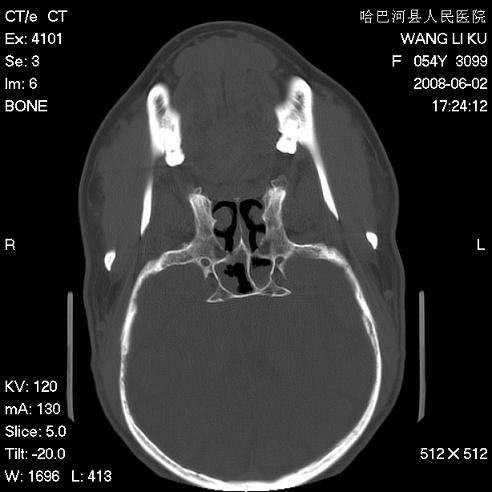

标题: CT13803:反复性鼻塞、流涕一年余 [打印本页]

标题: CT13803:反复性鼻塞、流涕一年余

1.全组副鼻窦炎2.双侧上颌窦积液

全组副鼻窦炎

1)全副鼻窦炎(左侧上颌窦黏膜下囊肿或息肉)。2)左眼眶肌锥内不规则小结节状软组织密度影;考虑为小血管瘤可能。建议行ct增强扫描检查。

全组副鼻窦炎,左侧肌锥内不规则形软组织肿块影,与眼外肌密度相当,左侧视神经受压,肿块与视神经及眼外肌分界清晰,眼外肌无增粗,眶壁无破坏,球后脂肪间隙不模糊,考虑良性改变,小血管瘤或神经源性肿瘤可能,建议增强扫描。

谢谢,增强扫描做了,眶内病灶与海绵窦同步明显强化,血管瘤